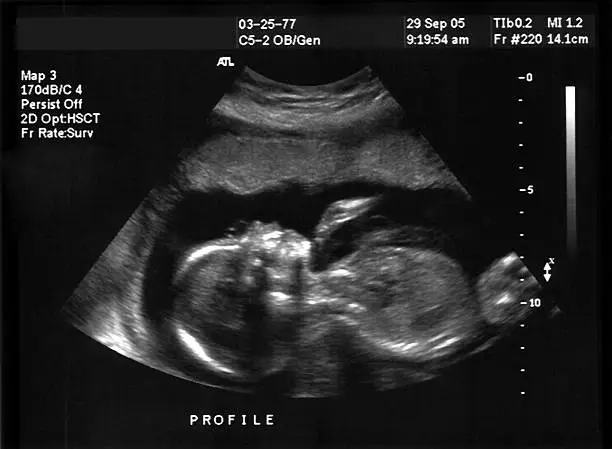

착상혈은 배란 후 수정된 난자가 자궁 내벽에 착상하는 과정에서 발생할 수 있는 출혈로, 이는 보통 배란 후 6일에서 12일 사이에 나타납니다. 수정란이 자궁벽에 자리 잡는 과정에서 자궁 내막의 일부가 손상되면서 소량의 출혈이 발생하게 되는 것입니다. 이 출혈은 보통 연한 분홍색이나 갈색을 띠고, 매우 가벼운 양으로 나타나며 길게는 며칠 정도 지속될 수 있습니다. 하지만 모든 여성들이 착상혈을 경험하는 것은 아니며, 개인에 따라 착상혈의 양상은 매우 다양하게 나타날 수 있습니다.

임신 초기의 hCG 호르몬 분비는 착상이 완료된 후부터 시작되며, 이 호르몬은 임신 여부를 감지하는 데 중요한 역할을 합니다. 그러나 착상혈이 발생한 즉시 hCG 수치가 급격히 증가하지 않기 때문에, 착상혈이 발생했다고 하더라도 임신 테스트기에서는 한 줄이 나올 수 있습니다. 이는 임신 테스트기가 소변에서 hCG 수치를 감지해야만 임신을 확인할 수 있기 때문입니다.

착상혈이 발생했다고 하더라도 임테기에서 한 줄이 나오는 이유는 임신 호르몬인 hCG가 아직 충분히 분비되지 않았기 때문입니다. 임신 테스트기는 소변 속에 포함된 hCG 호르몬을 감지하는 방식으로 작동하는데, 착상 초기에는 hCG 수치가 매우 낮기 때문에 임테기가 이를 감지하지 못할 수 있습니다. 보통 착상이 이루어진 후 7~10일 정도가 지나야 hCG 수치가 임신 테스트기에서 감지될 만큼 충분히 높아집니다.